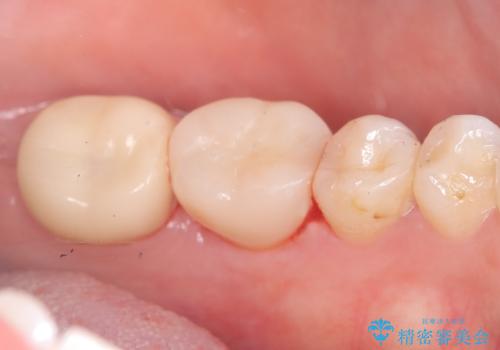

保存が難しい左下6番目の歯を抜歯し、左下8番目の歯(親知らず)を抜歯窩に移植しました。歯牙移植後の動揺防止のため暫間固定を行っています。

骨との定着を確認し、今後矯正治療を行う予定のためレジン冠をセットしています。